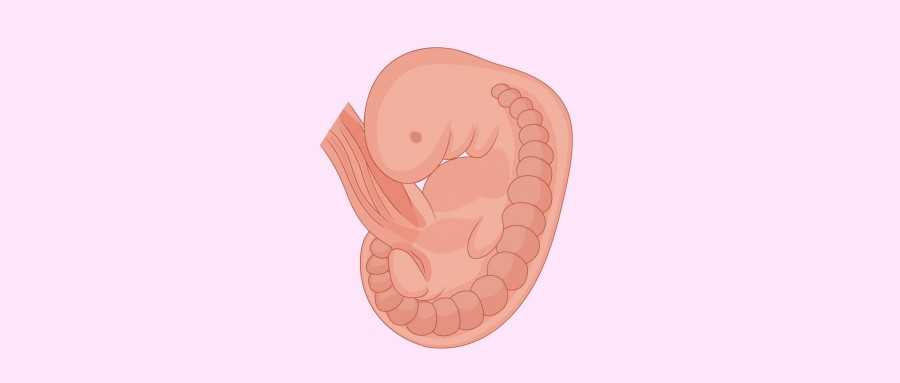

Внутренние органы крохи еще могут выступать в виде пупочной грыжи, но нет повода для беспокойства, ведь это совершенно нормальное явление.

Развивается мышечная система. Конечности малыша становятся более толстыми, движения усиливаются. Происходит формирование крупных суставов. Ручки малыша сейчас несколько опережают в развитии ножки, поэтому на ранних сроках они длиннее. Происходит формирование кисти: образуется ладошка, пальчики удлиняются, постепенно исчезают перепоночки между ними. Начинают формироваться закладки ноготков, пока в виде утолщения эпидермиса.

Важные изменения происходят в дыхательной системе малыша: начинается разветвление бронхиального дерева. Формируются главные бронхи.

Продолжается формирование сердца. Сейчас оно сокращается с частотой 130–150 ударов за минуту.

У эмбриона постепенно выпрямляется спинка, исчезает хвостик. Его головка склонена к туловищу, и пока она непривычно большая. Уже сформировались глазки малыша, но пока они закрыты веками. Еще не образованы свето- и цветочувствительные рецепторы сетчатки, они образуются на более поздних сроках.